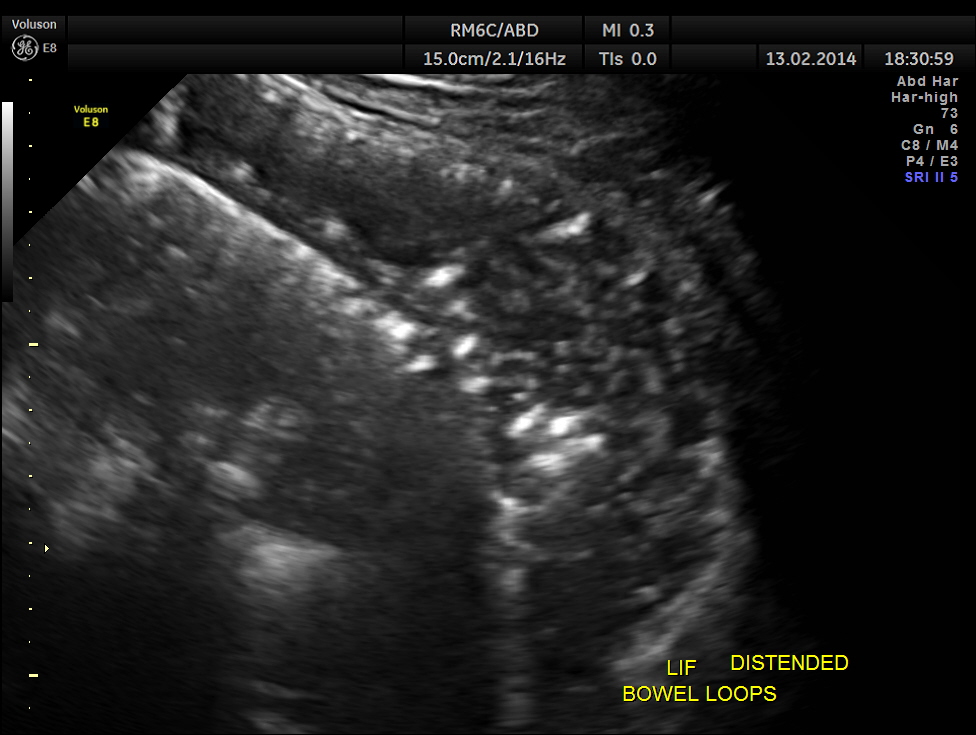

This was a 61 year old gentleman , who presented with complaints of acute abdominal distension , pain and history of constipation of 3 days duration . He showed the following findings :

grossly distended bowel loops